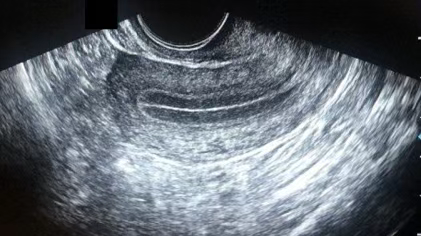

常见于月经第15-28天(黄体期),内膜厚度约10-14mm,超声下的表现为无三线征。

此时内膜在孕激素的主导下,进入分泌期,腺体变得更加弯曲、扩张,分泌大量糖原等营养物质,间质高度水肿,在一定程度上可能并不利于胚胎着床。

由于内膜回声过高,结构相对致密,血液供应和营养交换的效率可能会受到影响,从而导致胚胎难以顺利植入。

不过,这并不意味着 C 型内膜就完全无法实现成功移植,美国试管专家会根据具体情况,采取相应的措施来改善内膜状态,提高移植成功率。